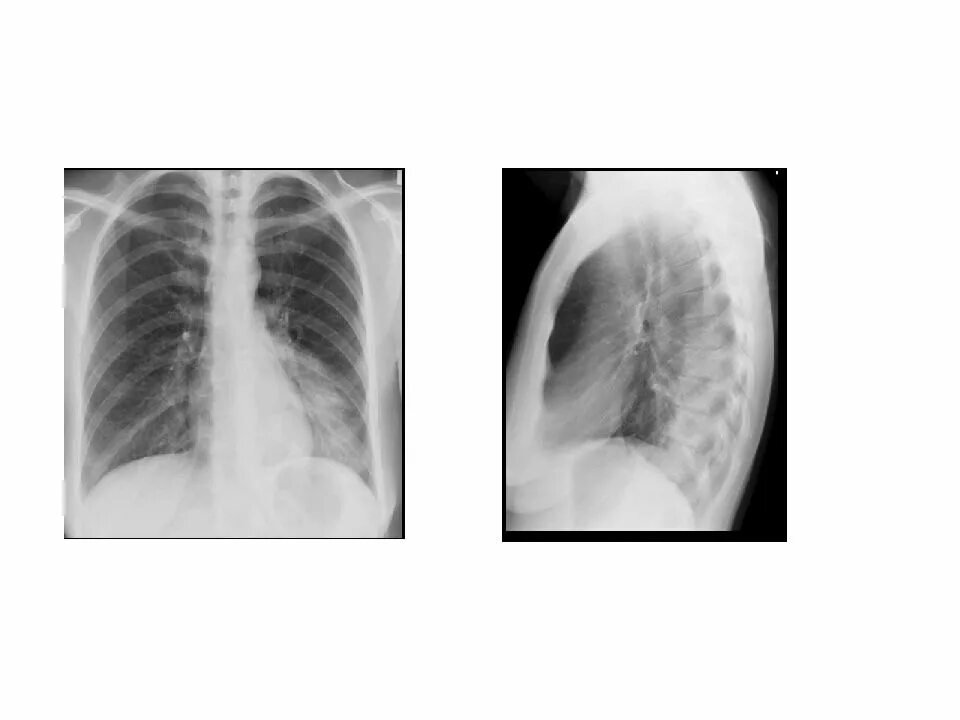

Синдром уплотнения ткани